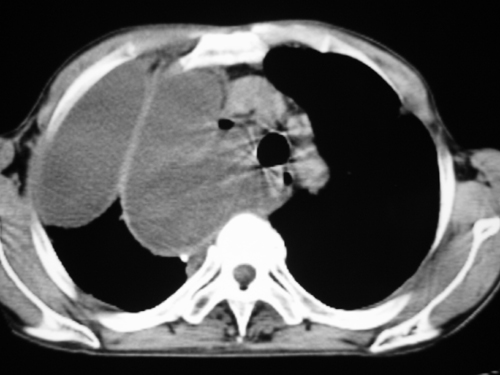

以下是引用yangyudong333在2008-4-29 5:46:00的发言:[br]1左上叶结节呈分叶状,边缘毛刺,考虑肺癌并纵隔淋巴结转移可能性大,结核待排,[br] [br]2右侧多发包裹性胸腔积液

以下是引用zsl6918在2008-4-29 9:15:00的发言:[br]右侧包裹性积液穿刺术后改变,肺内多发结节不除外转移可能。建议查胸水,问病史。